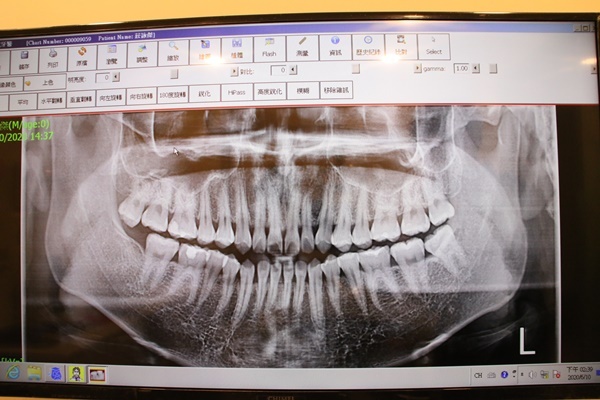

智齒約在16歲開始生長,建議大家可以每隔半年到新銳牙醫診所洗牙,順便檢查自己是否開始長智齒。

並不是所有智齒都需要拔;但如果覺得智齒萌出後沒什麼感覺,不痛不癢,也不要認為不需要拔,因為如果位置沒有長正,還是會影響健康。

是否需要拔,最好去新銳牙醫診所進行專業評估後再決定。